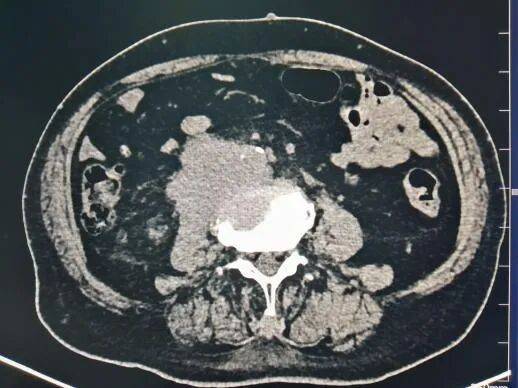

膀胱癌,椎体转移瘤并腹膜后软组织肿块形成。肿块与骨质破坏区相连,边缘毛糙